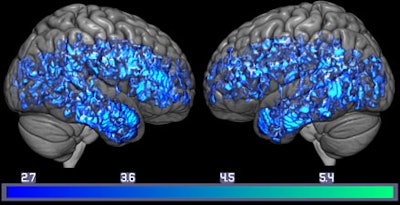

Subjects with mild cognitive impairment showed up to 38% less of the serotonin transporter in the brain, compared with the age-matched controls. In addition, when Smith and colleagues compared the imaging results with memory tests, they found that lower serotonin transporter levels correlated with lower test scores. For example, subjects with mild cognitive impairment had 37% lower verbal memory scores and 18% lower levels of the serotonin transporter in the brain's hippocampus, compared with healthy controls.